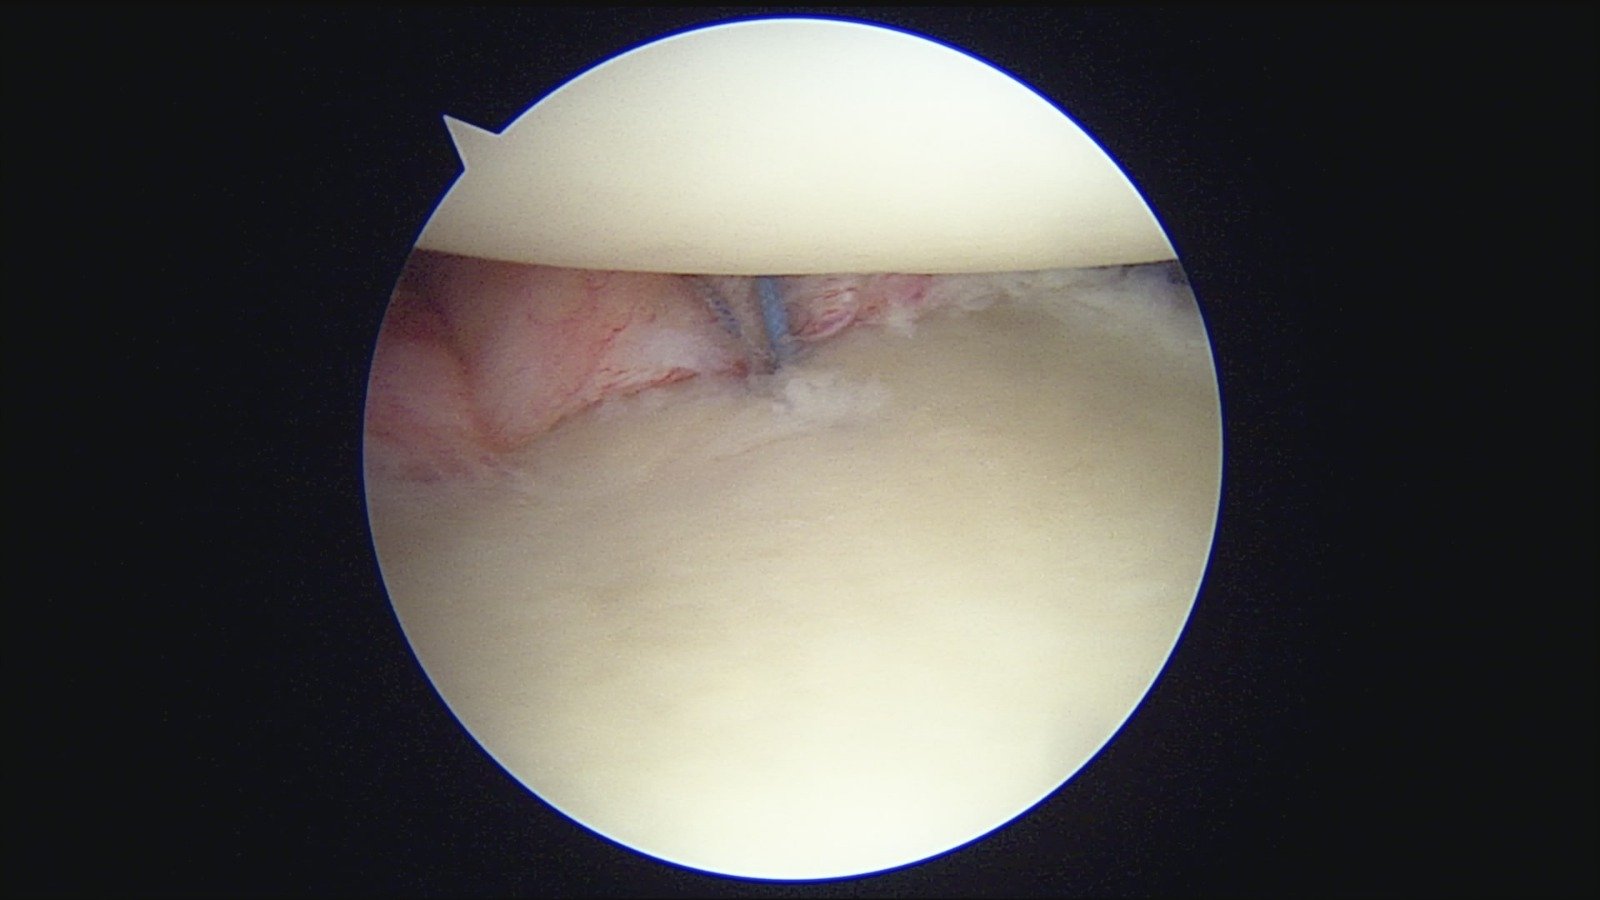

GalleryShoulder rotator cuff repair Meniscus root repair Meniscus repair Bankart repair for recurrent shoulder dislocation ACL reconstruction Machines Instruments